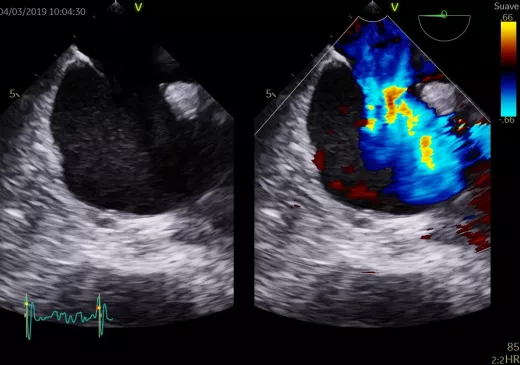

L’Hospital Universitari de Girona Doctor Josep Trueta, amb el suport econòmic de la Fundació Privada Daniel Bravo Andreu, obre la convocatòria de la 1a edició del Fellowship en tècniques d’imatge cardíaca avançades. Aquest Fellowship s’adreça a llicenciats en Medicina, amb títol d'especialista en Cardiologia, que vulguin fer una formació avançada en tècniques d’imatge cardíaca durant dos anys i compatibilitzar-la amb un contracte laboral al mateix Hospital.

Es tracta d'un programa innovador i únic que no tan sols representa un salt qualitatiu en la formació en tècniques d'imatge cardíaca a tot l’Estat, sinó que ofereix una oportunitat laboral excepcional. I és que, gràcies a la Fundació Privada Daniel Bravo Andreu, aquesta 1a edició del Fellowship en tècniques d'imatge cardíaca avançades està vinculada a un contracte de facultativa o facultatiu adjunt a jornada completa al Servei de Cardiologia durant els dos anys que duri el període formatiu.

Aquest Fellowship, codirigit per Ramon Brugada, cap del Servei de Cardiologia, i Sergi Moral, responsable de la Unitat d'Imatge Cardíaca Avançada, proposa una formació teòrica i pràctica reglada i avalada per la Universitat de Girona. També inclou el desenvolupament d’un projecte de recerca vinculat a alguna de les línies d’investigació establertes dins la Unitat. Amb aquest plantejament integrat es pretén iniciar un procés d'estandardització en la formació en tècniques d'imatge cardíaca avançades perquè sigui equiparable a la d’altres programes formatius internacionals.

L’objectiu final és que el professional adquireixi un coneixement i una pràctica avançada de totes les tècniques d'imatge cardíaca que hi ha, que aprengui el funcionament i la gestió d'una unitat d'imatge cardíaca avançada, que participi en les sessions docents del Servei de Cardiologia, que sàpiga supervisar estudis d'altres metges i tècnics, que tingui la capacitat d'anàlisi crítica dels articles publicats en la literatura mèdica i que sigui capaç de dur a terme futurs projectes d'investigació.

La Unitat ofereix una carta de serveis d'imatge cardiovascular de màxim nivell, que dona cobertura a tots els pacients adults i pediàtrics amb patologia cardíaca de la Regió Sanitària Girona. L'oferta assistencial inclou estudis d’ecocardiografia transtoràcica i transesofàgica en 2D, 3D i 4D, així com ecocardiografia d'estrès, tant farmacològic com d'esforç físic. També incorpora l'estudi i el seguiment de les cardiopaties congènites de l'adult i de l'infant.

La Unitat està acreditada per la Societat Europea de Cardiologia com a laboratori avançat en la realització d'ecocardiografia transtoràcica, transesofàgica i d'estrès.